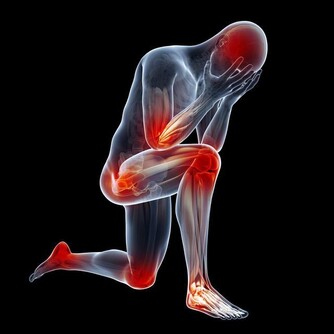

雖然炎症能在受傷的時候保護我們,但大家可能不知道,慢性炎症是非常危險的,它是包括心髒病、癌症在內的致命疾病的誘因。所以,在日常生活中吃一些抗炎食物,不僅可以幫我們減輕炎症帶來的疼痛,也有助於身體健康。

大蒜:殺菌預防胃癌

英國權威醫學雜誌上刊登了一個研究報告,經常吃大蒜能夠降低胃癌的死亡率。我們都知道幽門螺桿菌感染是胃癌的致病因素之一,而經常吃大蒜有助於預防胃癌的發生。因為大蒜中的大蒜素具有一定的殺菌、防癌功效,抑制有利於腫瘤生長的酶活性。所以本身有幽門螺桿菌感染的朋友不妨多吃一些大蒜,能預防胃癌發生。